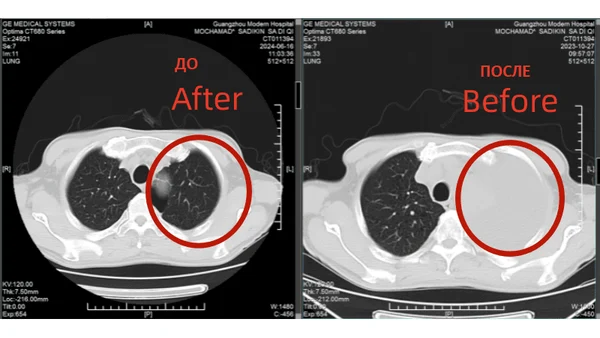

История надежды: Мохамад Садыкин из Индонезии побеждает рак легких IV стадии 68-летний пациент вернулся к активной жизни после комплексного малоинвазивного лечения в Гуанчжоу

Вызов: диагноз, который изменил всё

В октябре 2023 года у Мохамада Садыкина из Джакарты появились тревожные симптомы: непрекращающийся кашель, одышка и лихорадка. Обследование выявило рак левого легкого IV стадии с метастазами в печень и плевральным выпотом. Новость шокировала семью: Мохамад потерял 24 кг за две недели, а врачи в Индонезии не предлагали эффективных вариантов. Но его жена не сдалась: «Я сказала мужу: мы сделаем всё возможное. Рак можно победить!»

Лечение: комплексный подход. Мультидисциплинарная команда клиники разработала план: 1. Закрытое дренирование грудной клетки - для устранения плеврального выпота. 2. Интервенционная артериальная перфузионная терапия - доставка химиопрепаратов непосредственно в опухоль. 3. Таргетная терапия - блокировка роста раковых клеток. 4. Натуральная терапия - укрепление иммунной системы. «Процедуры напоминали иглоукалывание - без разрезов и боли», - отмечает пациент.

Результаты: от отчаяния к теннису

• Через 2 курса лечения: Кашель и одышка уменьшились, метастазы в легких и печени значительно сократились. • Через 6 месяцев: Плевральный выпот исчез, вес вернулся к норме. • Июнь 2024: Мохамад отдыхал на Бали и играл в теннис.

КТ-снимки подтвердили: опухоль в легком практически исчезла